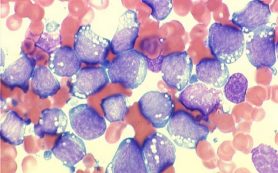

A Phase I/II study, led by investigators at The University of Texas MD Anderson Cancer Center, reports an investigational drug called tagraxofusp has demonstrated high response rates in patients with blastic plasmacytoid dendritic cell neoplasm (BPDCN), a rare but highly aggressive – and often fatal bone marrow and blood disorder – for which there are no existing approved therapies.

BPDCN patients historically have experienced poor outcomes and low response rates with a variety of cytotoxic chemotherapy approaches following diagnosis. While there are no approved therapies or standard of care, patients quite often receive chemotherapy approved for other blood cancers, and/or stem cell transplants, however the majority of patients are older or do not qualify for standard chemotherapy approaches.